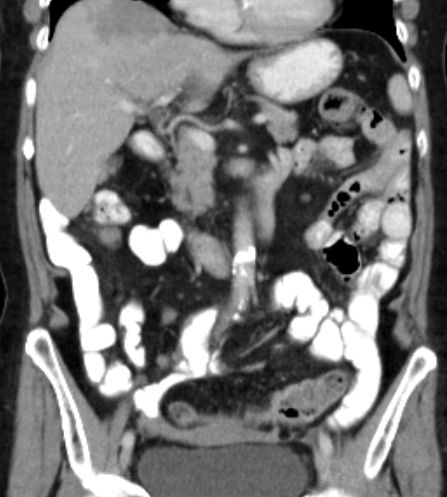

Spätrezidiv 77-jährige Frau bei der vor 13 Jahren ein Ovarialkarzinom behandelt wurde: Hysterektomie, bilaterale Adnexektomie, Omentektomie, Appendektomie, 6 Zyklen Carboplatin/Taxol

Nebendiagnosen: Mammakarzinom links 1977 (Ablatio + Axilladissektion)

Jetzt: peritoneale und Lebermetastasierung, mediastinale Lymphknotenvergrößerung.

Leberpunktion: Adenokarzinom. Die Tumorinfiltrate zeigen angedeutet papillären Strukturmuster. Immunhistologie: CK 7 stark positiv. Nukleär deutlich Östrogen sowie WT1. CK 20, CEA, CDX2, TTF1 negativ.